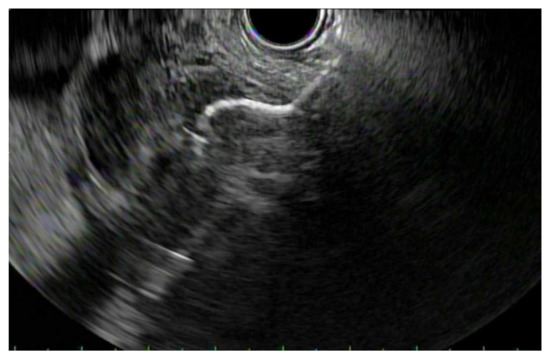

4.2. Biliary Obstruction: ERCP vs. EUS-BD